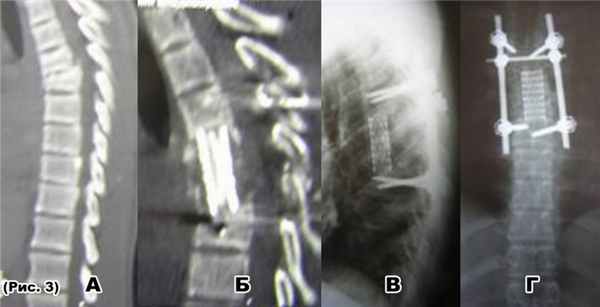

а) тотальная деструкция Th6- Th7-Th8 (туб. спондилитTh6- Th7-Th8);

б) удаление телTh6-Th7-Th8 позвонков боковой спондилодез мешем с ауторебром;

В) транспедикулярнаяфиксацияTh3- Th4-Th5-Th10- Th11 позвонков.

в) транспедикулярнаяфиксацияTh5-Th6- Th11- Th12 позвонков.